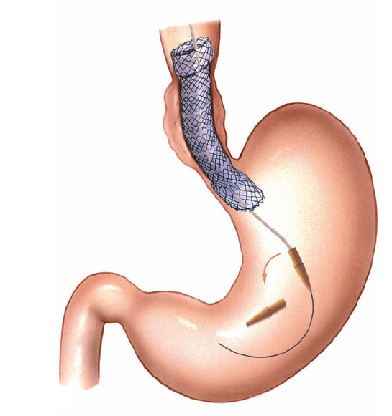

- Dilatadores flexíveis: uma série de sondas graduadas (espessura crescente) chamadas de sondas termoplásticas podem ser usadas. Estes são tubos que passam através do esófago para o estômago. Os tubos utilizados tornam-se progressivamente maior, até que o tamanho desejado seja atingido

- Balões dilatadores: a dilatação do esôfago pode ser feita usando balões durante a endoscopia. A endoscopia flexível permite ao examinador visualizar diretamente a estenose. Um balão é introduzido pelo canal do aparelho até a zona de estreitamento. Ele é então insuflado com água até uma certa pressão, que é pré-ajustada para uma dada circunferência. Quando insuflado, torna-se em forma de salsicha, esticado, e faz com que a estenose se abra.

Tratamento da Acalasia

- A Acalasia requer um tipo de balão específico, mais longo e maior, chamado de balão pneumático. Nesta situação, as fibras musculares espásticas na parte inferior do esôfago são esticadas.

Dilatação do esôfago é a técnica utilizada para esticar uma parte bloqueada ou estreitada do esôfago. Este procedimento é usado quando uma parte do esôfago tornou-se tão estreita que se torna difícil, ou mesmo impossível e doloroso para engolir.